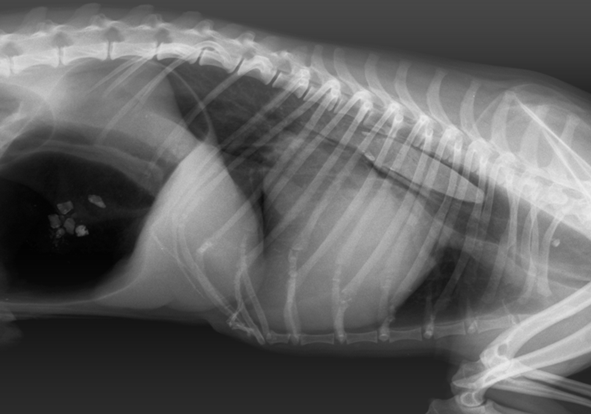

Диагностика инородных тел

Диагностика инородных тел пищевода и желудка включает в себя обязательное использование инструментальных методов, таких как: рентген, контрастная рентгенография пищевода и желудка, эзофагогастроскопия.

Существуют инородные тела рентгеноконтрастные – они визуализируются на рентгене, и не рентгеноконтрастные – они не визуализируются на рентгене (например, дерево). Дополнительное введение рентгеноконтрастных веществ (сульфат бария, йодсодержащие препараты), при проведении рентгена пищевода и желудка, позволяют в некоторых случаях определить не рентгеноконтрастные инородные тела (фото 1).

Наиболее объективной диагностикой является эндоскопический метод – эзофагогастроскопия. Инородное тело в пищеводе у собаки и у кошки можно определить с помощью эзофагогастроскопии и даже выявить последствия их пребывания в пищеводе и желудке, оценить состояние слизистой оболочки (фото 2, 3).

Особую проблему представляет собой хирургия пищевода грудного отдела. Операция проходит в грудной полости в условиях искусственной вентиляции лёгких. Для проведения подобного оперативного вмешательства необходимо чётко знать местоположение инородного тела в пищеводе, так как разное положение определяет место доступа в грудную полость. Для этого необходимо провести эзофагогастроскопию животному (фото 4,5,6,7).

Фото 4а, 4б, 4в: Кость в пищеводе грудной части у йоркширского терьера

На фото 5а, 5б, 5в: Кость в пищеводе грудной части у грифона

Фото 6а, 6б, 6в: Инородное тело (игрушка) в желудке лабрадора

На фото 7а, 7б, 7в, 7д: Иголка в желудке у кокер-спаниеля